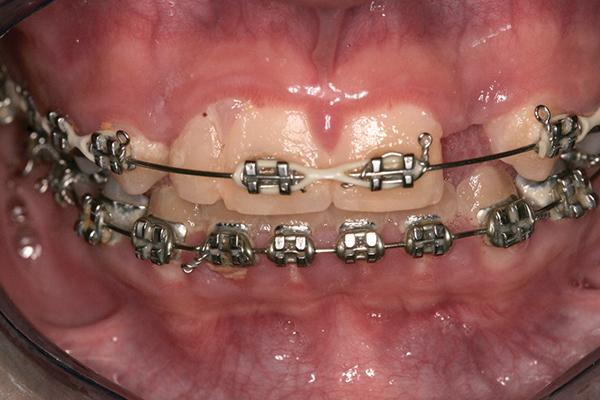

The patient saw her pediatric dentist for regular maintenance, returning to the orthodontist for yearly assessments until she reached the age of 12 years, 1 month, at which time orthodontic therapy commenced. Fixed edgewise orthodontic therapy was performed for 2 years and 7 months to create an ideal space for implant tooth No. 10, close the diastema between teeth Nos. 8 and 9, and coordinate the facial-to-maxillary dental midlines (Figure 6). When the appropriate coronal and apical mesial-distal space was created by the orthodontist for implant placement (age 14 years, 3 months), a resin-bonded retainer was fabricated for optimal stability of coronal and root position,29 and cemented with a resin cement (Figure 7 and Figure 8). Also, a conventional removable retainer was delivered.

Fig 6. Fixed edgewise orthodontic therapy.